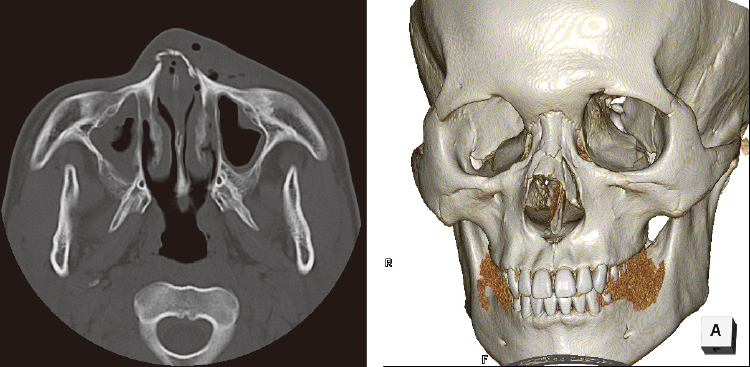

鼻骨骨折のCT画像診断のポイントは?治療、分類(nasal fracture)、症状は?